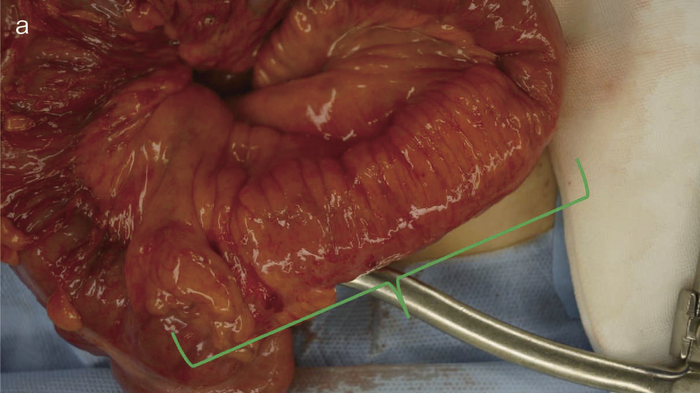

図35 術中所見と術式

術中所見では,肝転移,腹膜播種はなく,回盲部周囲のリンパ節には軽度の腫大を認めたものの,明らかな転移を疑う所見はなかった。回腸末端部に回盲弁から連続した壁硬化とfat creepingを伴う病変を認めた(図35a緑の範囲)。回結腸動脈が主な支配血管であり,触診上壁の硬化を認めた部から口側に5 cmまでの回腸と上行結腸を切除した。術中,迅速病理診断で202リンパ節に転移がないことを確認し,回結腸動脈根部まで郭清した。

図36 切除標本

切除標本の肉眼像では4 cm長の全周性腫瘍でvillous様の構造を呈しており,この肛門側に縦走潰瘍を伴う5 cm長の病変(炎症)を認めた。

病理組織検査所見では,well differentiated adenocarcinoma,m,ly0,v0,pN0,p53弱陽性,全層性炎症で非乾酪性類上皮性肉芽腫を認め,診断後の経過は短いものの,CDの慢性炎症から生じた炎症性発癌と考えられた。

CD腸管癌では周囲病変と癌あるいはdysplasiaの範囲を区別することは困難で,本症例のように切除範囲が長くなる場合もあり得る。